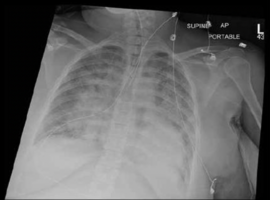

Citation: Karamchandani K, Benrud J and Swick JT. Acute Pulmonary Edema in a Pregnant Patient with Undiagnosed Levo-Transposition of the Great Arteries. Case Rep Clin Cardiol J. 2022; 2(1): 110.